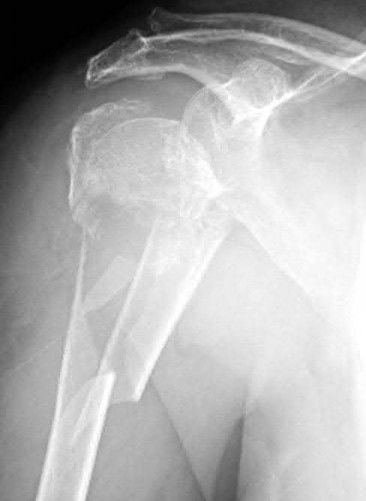

A 70-year-old woman falls down a flight of stairs and sustains the injury shown in Figures A and B to her dominant upper extremity. She lives alone and has no other medical history. Which of the following surgical options is best to minimize complications for this fracture pattern?

This patient has a complex proximal humerus fracture with metaphyseal comminution and poor bone stock. Cemented reverse total shoulder arthroplasty (rTSA) using a long stem prosthesis and tuberosity repair is indicated.

Proximal humerus fragility fractures are hard to treat because of comminution and poor bone stock. AVN is common with glenohumeral fracture-dislocation. Hemiarthroplasty (and standard total shoulder arthroplasty, TSA) is unreliable because of dependence on tuberosity healing. rTSA is recommended for fractures in patients >70 years with severely comminuted fractures, high likelihood of head AVN, and poor tuberosity bone quality (osteoporosis or comminution).

Bufquin et al. retrospectively reviewed the use of rTSA for treatment of 43 patients with 3- and 4-part proximal humerus fractures. They found satisfactory elevation (97°), ER in abduction (30°), constant scores (44) and modified Constant scores (66%). Complications included calcification (90%), tuberosity displacement (53%) and scapular notching (25%). They concluded that rTSA was a good procedure because it provides pain relief and easier functional recovery in spite of failed tuberosity healing.

Anakwenze et al. systematically reviewed acute proximal humerus fractures. Frequency weighted range of motion was flexion 122°, abduction 97°, ER at neutral 18°. Tuberosity repair yielded higher ER compared to no repair.

Scapular notching was the most common complication (32%). They concluded that rTSA patients tended to be elderly women with 4-part fractures, had good pain control but residual dysfunction.

Jobin et al. reviewed rTSA for management of proximal humerus 3- and 4-part fractures. They note >50% of cases have tuberosity resorption. They recommend repairing the greater tuberosity to restore infraspinatus/teres minor function which improves external rotation strength. Greater tuberosity malunion is not a result of secondary displacement, but rather, from intraoperative malreduction. Lesser tuberosity repair should be performed if there is significant bone loss or intraoperative anterior instability.

Figures A and B are AP radiograph and 3D reformatted CT scan showing comminuted proximal humerus fracture dislocation. Illustration A shows rTSA performed with distal cementation of a long stem prosthesis and cerclage fixation of the proximal shaft and the tuberosity fragments.